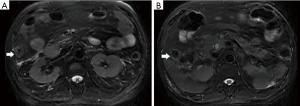

Among the AP patients, wall thickening involved duodenum (Figure 1) (27%), ascending colon (26%), stomach (20%), transverse colon (15%), jejunum (Figure 2) (14%) and ileum (6%). Dilatation of the gastrointestinal tract was seen in 8% (Figure 2, Table 2).

During treatment, 62 patients had follow up MRI examination, 16 of whom (26%) had a gastrointestinal tract abnormality on follow up examination, significantly lower than that on the initial MRI (P<0.05) (Figures 3-7). The frequencies of gastrointestinal tract abnormalities for initial and follow-up MRI examination are shown in Table 3. The difference for the frequencies of stomach, duodenum, jejunum, ileum, ascending and descending abnormal changes between before and after the treatment had statistical significance (P<0.05). There was no difference of transverse colon and bowel dilatation before and after the treatment (P≥0.05).

It was found that gastrointestinal tract wall thickness was greatly thinner after treatment (P<0.05) (Table 4).

In the follow-up MRI exam, the structure of gastrointestinal tract restored to revert in MRI, coinciding with relief of abdominal pain, recovered appetite, cessation of hematuria, amylase recovery and anal passing gas.

In this study gastrointestinal tract wall thickening was the most common finding in AP patients. Inflammatory substances can stimulate the gastrointestinal tract in patients with AP, leading to the excessive output of gastric juices and subsequent mucosal and submucosal edema (27). Some patients exhibit a three-layer structure referred to as the “target sign” (28). Tolan et al. (29) considered this pattern acute wall edema, and noted a direct correlation with inflammatory activity. In this study we found most AP patients exhibited gastrointestinal tract wall thickening, some with a stratified appearance on MRI that was similar to the “target sign” (28). After treatment, the mural stratification resolved on follow-up MRI. Our results suggested that the thickened intestinal wall in AP patients is derived from acute wall edema and can resolve soon after treatment.

AP inflammation can spread through connected anatomic compartments, or across biofilms damaged by pancreatic enzymes (32,33). The closer to the pancreas, the more obvious the impact on the affected tissues and organs. As duodenum, ascending colon and descending colon are retroperitoneal and stomach, jejunum and transverse colon are close to the pancreas (34), we found these organs could be frequently involved in this study. In contrast, the sigmoid colon, far from the pancreas, showed no involvement in this study.